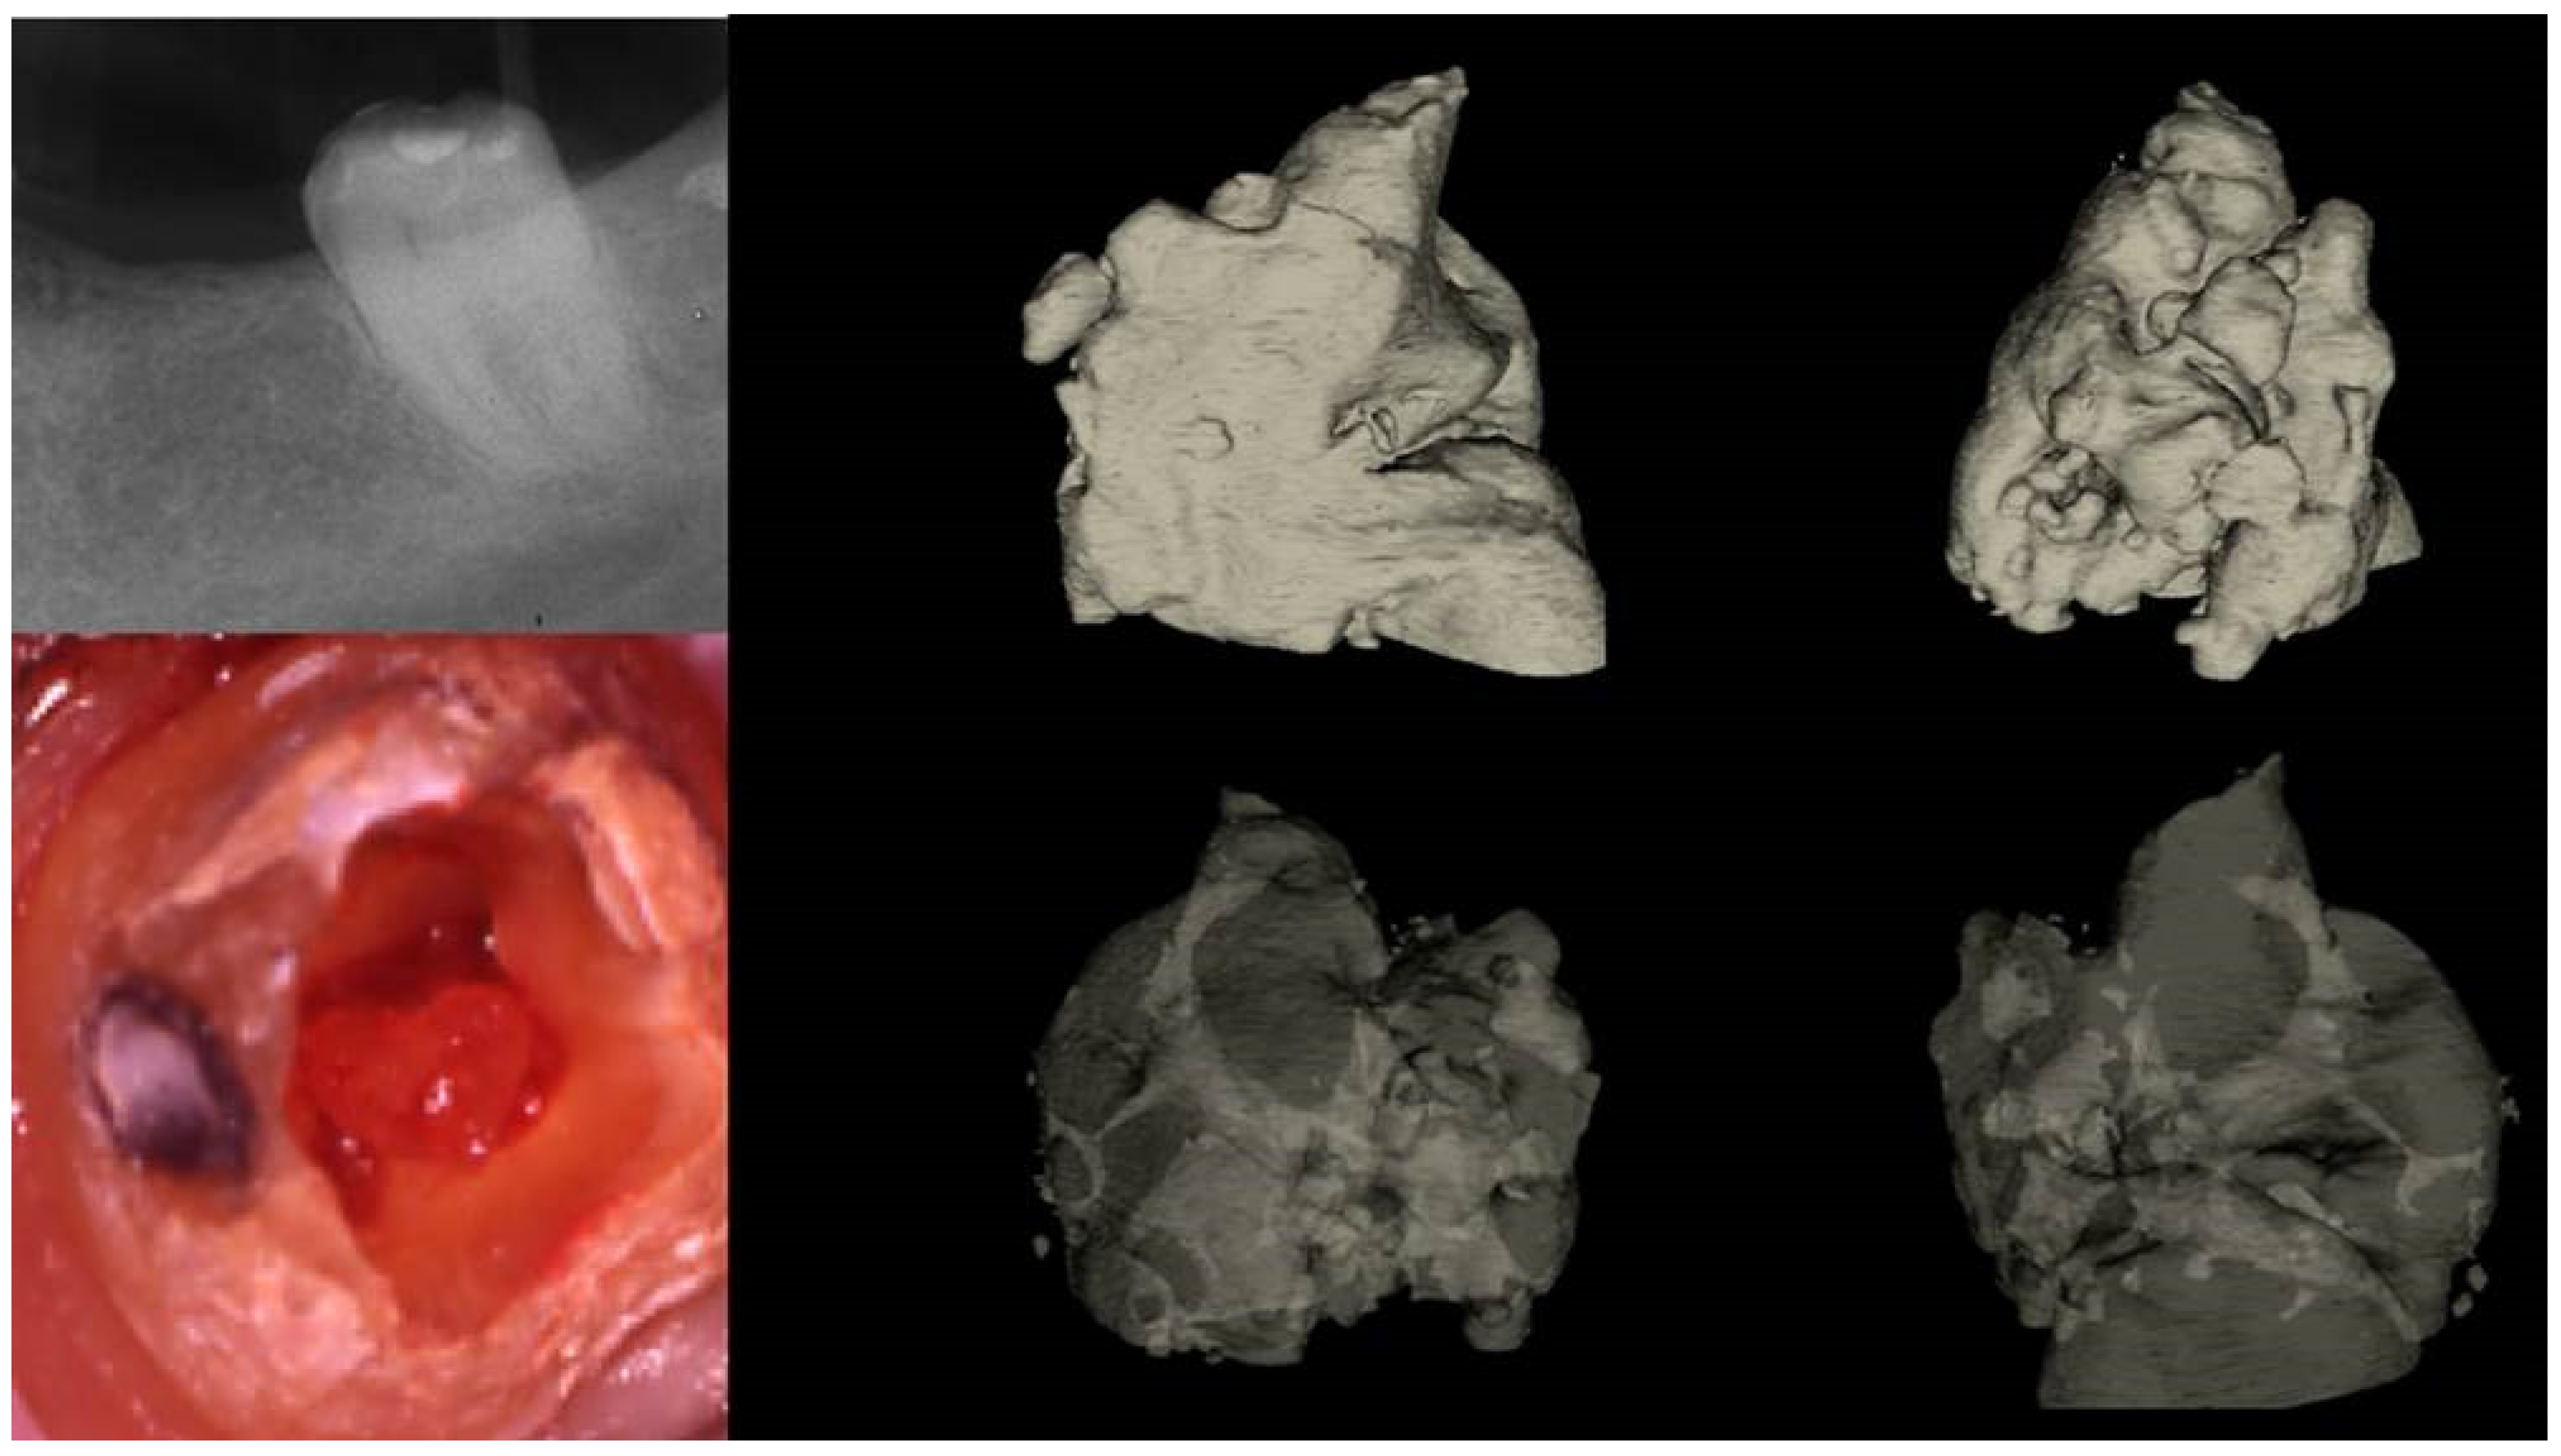

Figure 11.

(I) (A) Preoperative panorax focused on the impacted right maxillary canine, revealing a large lesion. (B) Two-year follow-up panorax after the surgical removal of the lesion revealing healing. (C,D) Periapical radiographs reveal recurrent disease 6 years after the surgical intervention. Notice that the maxillary canine was brought in occlusion with orthodontic treatment, but the canal was rendered radiographically blocked. (E,F) CBCT axial slices evaluate the magnitude of the periapical lesion and the root canal calcification of the maxillary canine. (II) (A,B) Clinical microscopic image from two different angles of the previously initiated access cavities. Notice the gray spot indicating the calcified root canal orifice (yellow arrow). (C) Clinical image of the initial troughing of the calcified canal with a round long shafted bur (Munce bur). (D) EDM file during the buckling resistance activation test negotiation technique. (E) Clinical image of the calcified orifice after the first BRAT stroke. Canal negotiation with the 08 D-finder file is now possible. (III) A Preoperative periapical radiograph. (B) Periapical radiograph demonstrating the initial negotiation of an 08 D-finder after the first BRAT stroke. (C) Periapical length determination radiograph. (D) Postoperative radiograph. (E) One-year follow-up periapical radiograph. (F–H) Three-year follow-up cbct reveals complete healing of the periapical lesion (axial slices) (clinical images and radiographs courtesy of Dr. Chaniotis Antonis). Red arrows indicate the calcified canal location, and Yellow arrows indicate the impacted canine. The white circle is the projection of a nose piercing ring in the radiograph (not a symbol).

The static-guided technique involves the utilization of a guiding template in conjunction with cone beam computed tomography (CBCT) to aid in the localization of severely calcified root canals (Figure 15) [20,44,47,48,50]. This technique relies on the design of the guide, which is based on the anatomical features of the root canal and the surrounding tooth structures, obtained through CBCT images and either an impression or intra-oral surface scan, respectively (Figure 15) [51].

Figure 15.

(I) (A) Preoperative periapical radiograph of calcified maxillary central incisor diagnoses with apical periodontitis. (B) Preoperative clinical buccal view of the maxillary central incisors. (C) Preoperative cbct scanning of the maxilla. (D) Preoperative intraoral scanning of the maxilla. (E) Matching the CBCT scanning with the intraoral scanning and designing the guide in the codiagnostiX 10.5 software. (II) (A) Three-dimensional printed surgical guide with lateral windows to check the adaptation. (B) Intraoral fitting of the surgical guide. (C,D) Pencil marking of the access location point lingual and buccal view. (E) Access point mark to remove the enamel. (F) Fitting of the surgical guide and drilling the initial pilot hole. (G) Clinical palatal view of the guided access. (H) Intraoperative radiograph of the pilot drill (Steko bur). (I,J) Length determination and gutta-percha fitting radiographs. (K) Postoperative radiograph. (L) Two-year follow-up radiograph reveals healing (courtesy of Dr. Hugo Sousa Dias).

Specialized software, such as coDiagnostiX 10.5 (Dental Wings Inc., Montreal, Canada), is employed to superimpose CBCT data and 3D intra-oral scans, facilitating virtual planning of the access cavity [47,51]. Subsequently, a 3D virtual template is generated to produce the physical model of the endodontic guide, which guides the bur into the calcified root canal [47,51]. Static-guided access in cases of pulp canal obliteration (PCO) in anterior teeth has been previously documented in the literature and is described as a safe and predictable technique for minimally invasive access to calcified canals. This approach aids in preserving tooth structure, avoiding technical errors, and improving long-term prognosis [48,52]. Krastl et al. [53] were pioneers in describing the static-guided technique in vivo, specifically on a maxillary central incisor with PCO and apical periodontitis. Originally developed for implantology, this technology has been adapted for use in endodontics, surgery, and conventional access [54]. The static-guided technique involves accessing and locating root canals through a guiding template created via tomographic planning [48,52]. The guiding template sleeves direct the position of the access burs, enhancing perforation precision during access and ensuring adequate tomographic planning (see Figure 15). Ex vivo studies have demonstrated the high accuracy of the guided endodontics technique. Buchgreitz et al. [55] concluded that the mean distance between the drill path and the target was less than 0.7 mm, while Zehnder et al. [43] showed low deviations between planned and prepared access cavities, with mean angle deviations of 1.81° [56]. The accuracy of guided splints depends on various factors, including the type of support and study, technique used to produce the template, planning software, discrepancy between the drill and cylinder guide, degree of wear of the drill, and number of guides used [56]. However, guided templates are associated with limitations, such as inaccuracy, high economic cost, long therapeutic time, and potential complications [56].